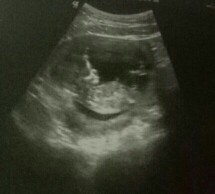

boy or girl?☺??

Ano sa tingin niyo guy's? boy or girl? Excited na ako sa gender ni baby☺?

Parang boy kasi may lawit hehe

parang boy.. ilang weeks kna?

Parang boy sis 🥰🥰

Parang baby boy! 💕